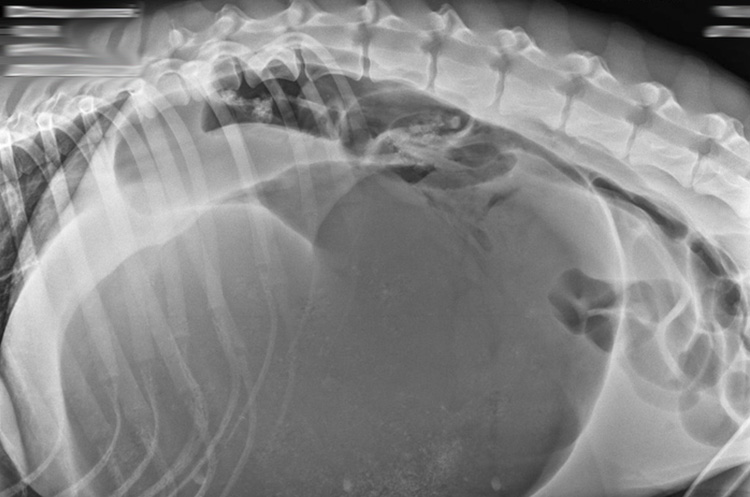

Aby pro veterinárního lékaře nebyl psí pacient s torzí žaludku strašákem, k tomu chce přispět i tento seminář. Zopakujeme patofyziologii a diagnostiku tohoto akutního a život ohrožujícího stavu u psů, jeho léčbu a i jak komunikovat v tomto těžkém okamžiku pro každého majitele. To vše za přispění lékařů z Veterinární kliniky Medipet.